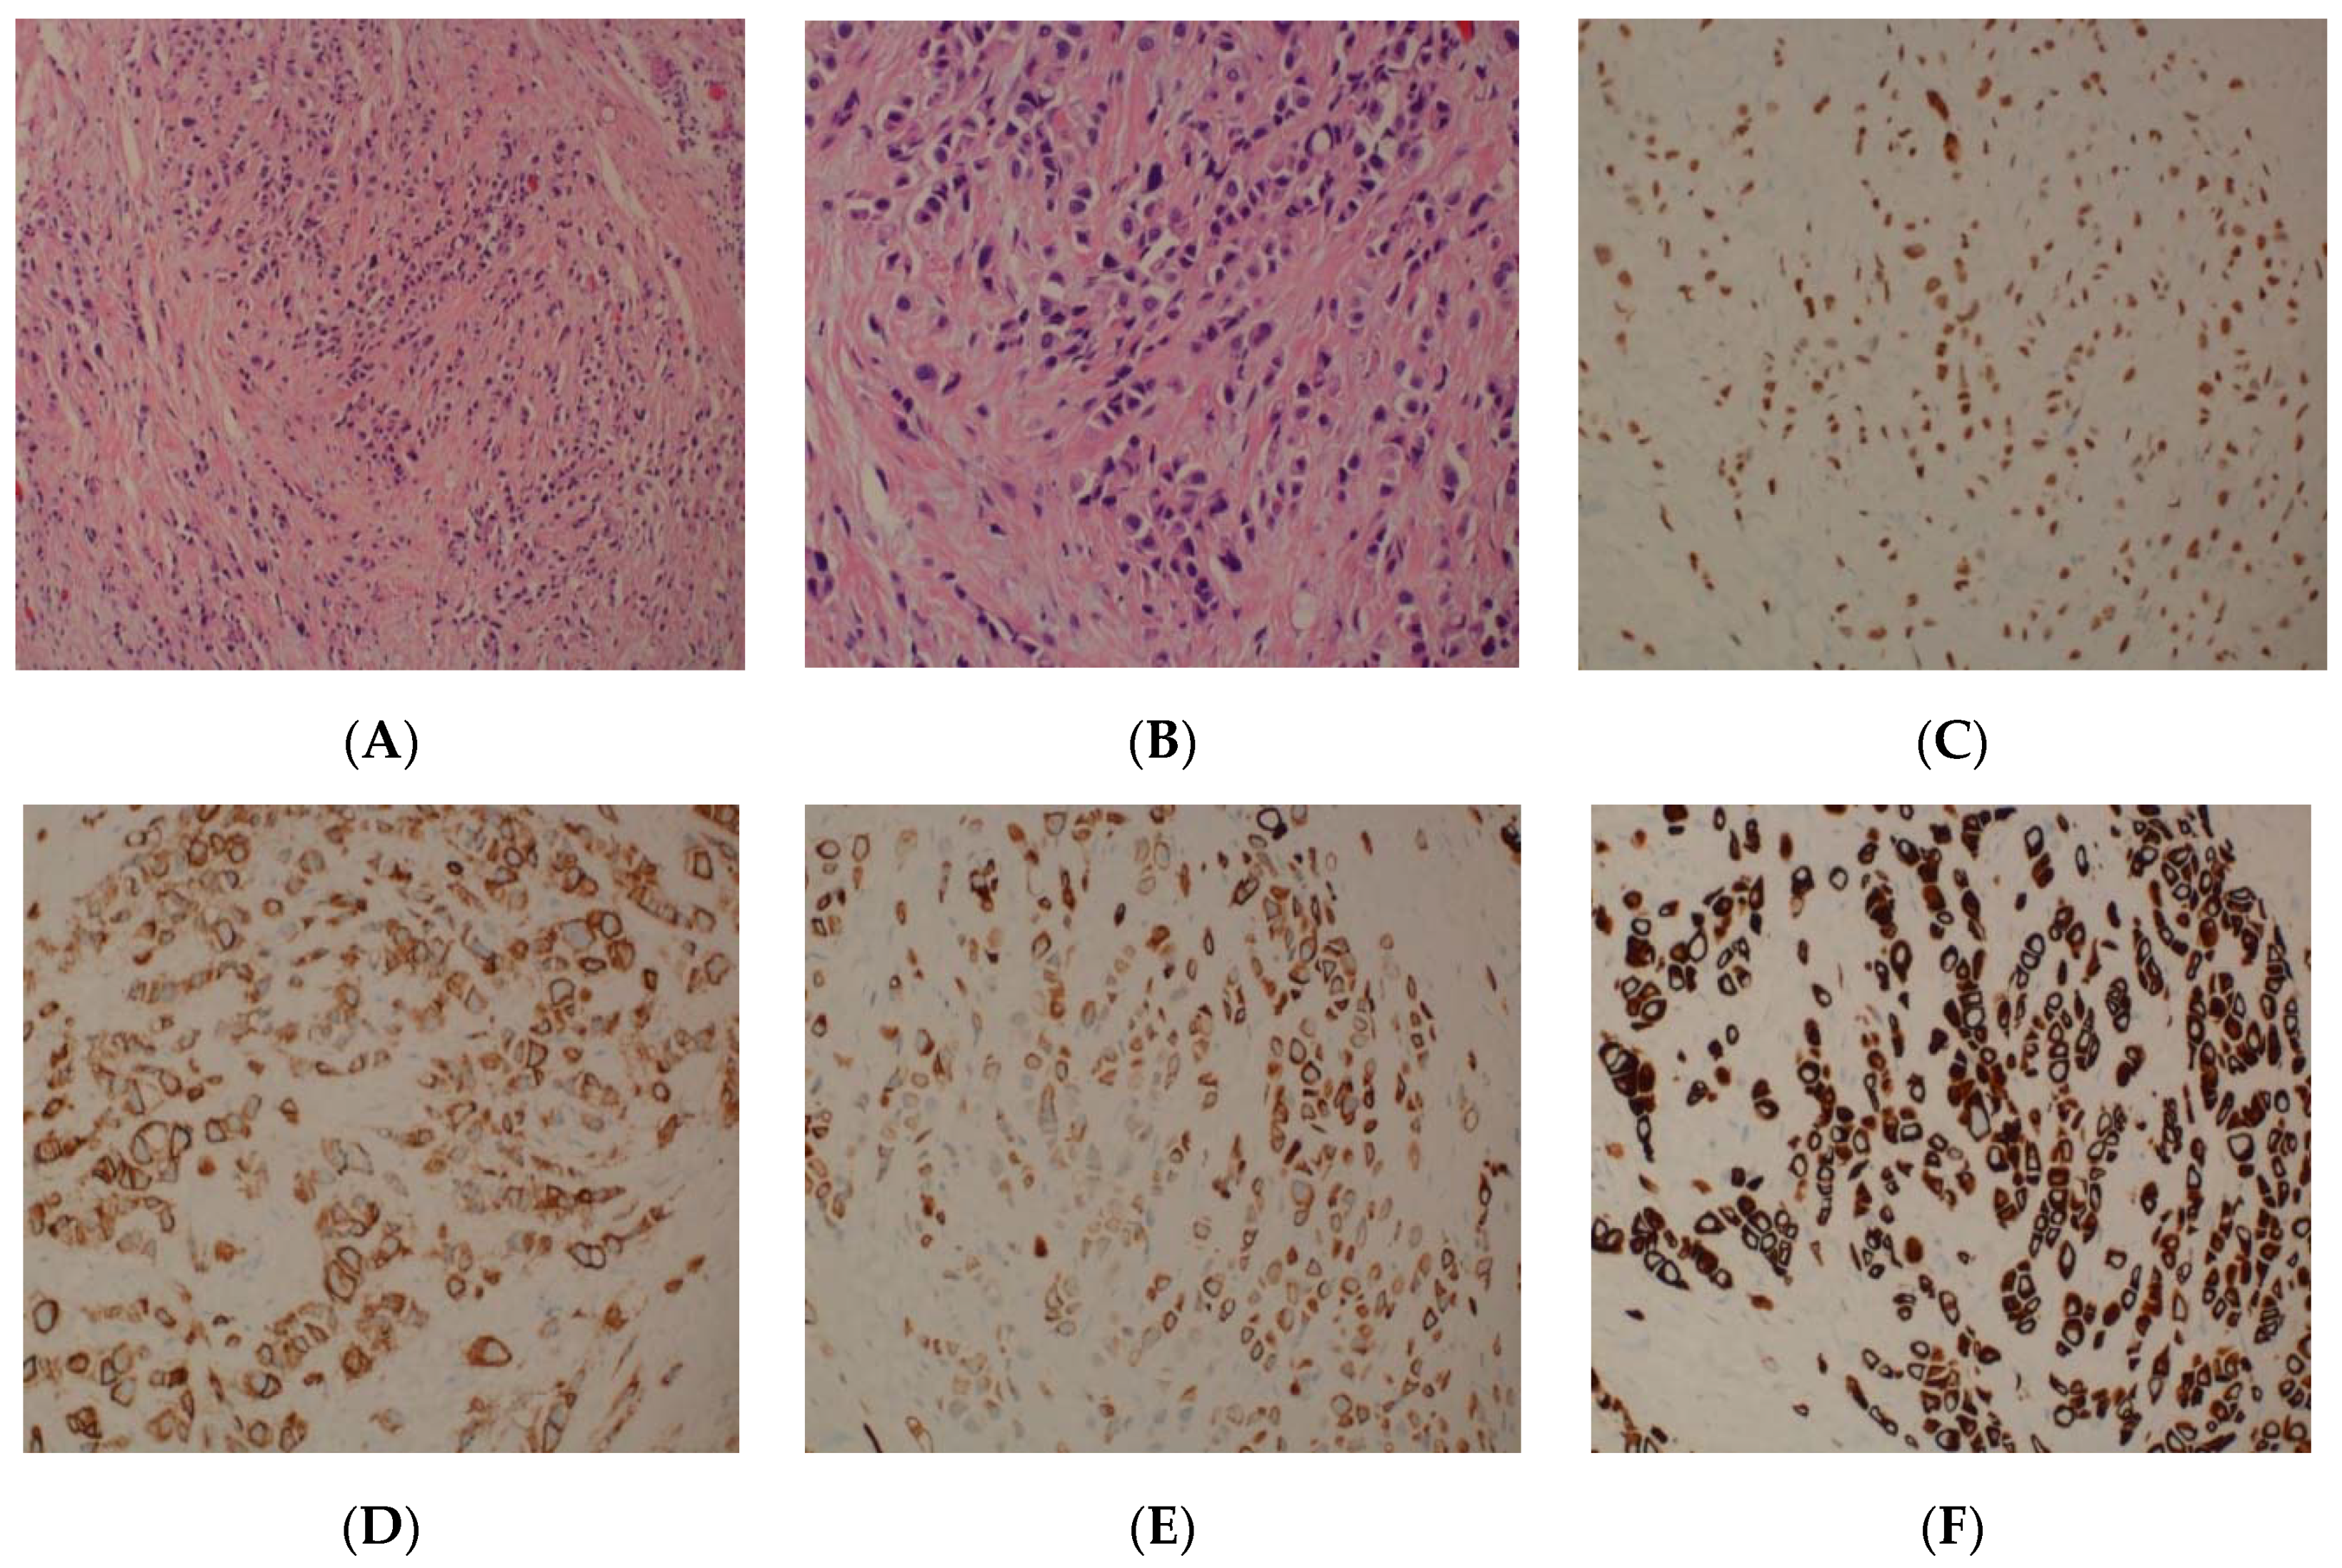

2. Case Series